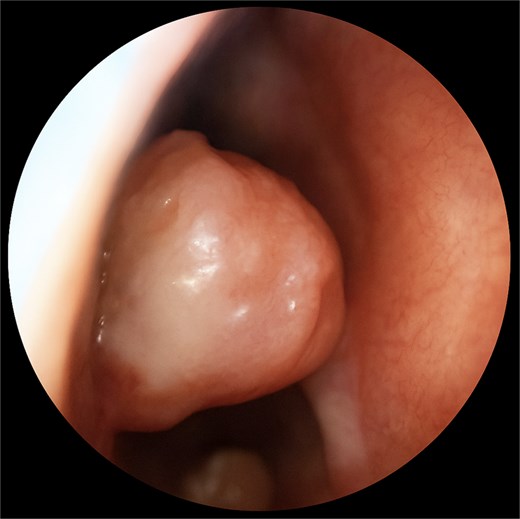

A 67-year-old male presented to our outpatient office with complaints of increasing bouts of right sided nasal bleeding for the preceding twelve months. He had been able to control the epistaxis with pressure and oxymetazoline nasal spray; however, a recent Emergency Room visit for persistent nasal bleeding prompted a referral to our office. The patient denied nasal trauma or other sinonasal problems in the past or present. He was not taking any anticoagulant or antiplatelet therapies. Nasal endoscopy revealed a soft, pale, non tender mass on the caudal end of the right inferior turbinate. Coagulated blood was noted over the anterior portion of this mass, without any vascular prominence or bleeding appreciated over the septal wall. This indicated the nasal mass was the site of recurrent epistaxis. Non-contrast computed tomography (CT) of the sinuses (Figs 1 and 2), showed a soft tissue prominence at the same area seen on endoscopy (Fig. 3).

Coronal non-contrast CT scan images of soft tissue lesion on right inferior turbinate.

Differential diagnosis included sinonasal inflammatory polypoid disease, nasal papilloma, sinonasal haemangioma, malignancy, amongst others with a glomus tumour lower on the differential given the rate of occurrence in the nasal cavity. The mass was excised using scissors at its broad base. An oscillating shaver blade was used on the anterior end of the turbinate and an absorbable sponge was placed for hemostasis.